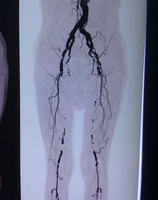

血管外科副主任崔文军亲自与邹大爷家属做术前沟通,通过画图详细说明了此次的手术方式及可能存在的风险,最终取得邹大爷家属的理解和赞同。手术由王兵教授亲自操刀,通过腹膜后入路,在不干扰肠管的情况下,成功露出左侧的髂动脉及股总动脉,但术中血管的情况还是出乎大家的意料,整个髂动脉都如骨头般坚硬,没有丝毫的弹性,大大增加了手术难度。最终,王兵教授凭借精湛的技术,在患者股总及髂外动脉行多个小切口(图2),不仅取出了陈旧血栓(图3),也完整剥脱了髂动脉增生的内膜及斑块(图3)。分段小切口的目的,一方面可完整剥脱斑块,最重要的是可以有效降低血管的再狭窄率,起到良好的远期通畅效果。术后当天邹大爷就感觉到自己的左脚没有那么凉、那么疼了。第二天,王兵教授到病房楼查看邹大爷术后恢复情况,邹大爷紧紧握着王兵教授的手说:“谢谢王教授,让我终于睡了个安稳觉!”术后,在施敏护士长带领的护理团队精心护理下,目前邹大爷康复良好,未出现任何并发症。

图2图3